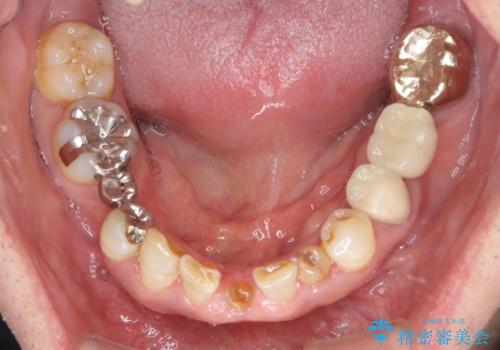

- 乳歯や矮小歯が多くある前歯部の審美障害が気にして来院された患者様です。

上顎の矮小歯は隙間が多く、歯軸の傾斜も大きかったため、部分矯正により補綴治療前に歯の位置を整えることとしました。

下顎の乳歯は支台歯として機能することは困難と思われたので、事前に抜歯をし、上顎の矯正治療終了のタイミングに合わせて、セラミックブリッジにて補綴治療することとしました。